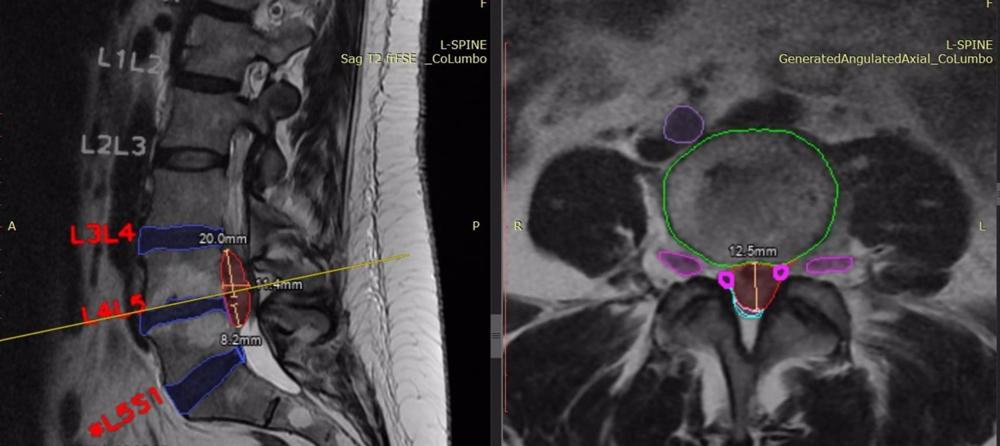

Unilabs, proveedor de servicios de diagnóstico, se ha asociado con SmartSoft Healthcare para implementar en España su solución de inteligencia artificial (IA), ’CoLumbo’, con el fin de mejorar la lectura y los informes de resonancia magnética de columna lumbar.

En la primera fase de implantación, Unilabs España aprovechará esta solución de última generación para analizar 17.000 exámenes anuales, lo que permitirá a los radiólogos elaborar informes más precisos y eficientes. En una segunda fase, se procesarán 25.000 exámenes anuales adicionales con ’CoLumbo’, lo que reforzará aún más las capacidades de diagnóstico de Unilabs España.